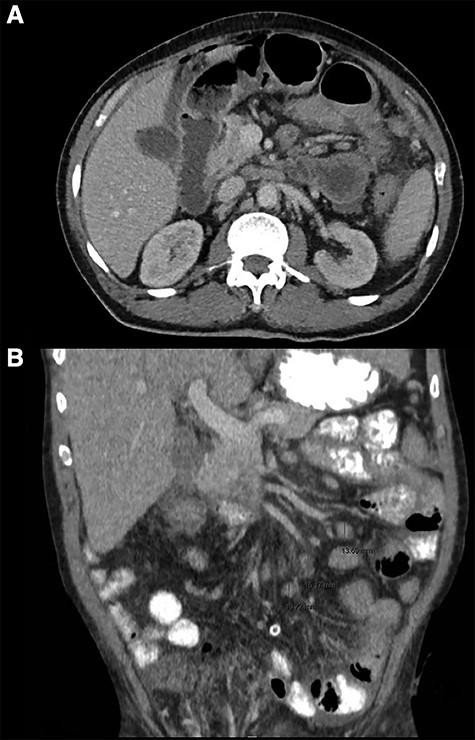

Intra-operative photos. (A) Site of the larger jejunal perforation, contained due to adhesion to the peritoneum. (B) Large studded white bowel mass with numerous peritoneal and omental depositions.

Emergency laparoscopy was performed the same night. Intraoperative findings included fecal peritonitis and numerous diffuse white studs on the peritoneum, smaller intestine and mesentery, raising the suspicion for peritonitis carcinomatosis (Fig. 2). The right inguinal hernia was observed, containing non-incarcerated omentum and small bowel. The aspect of both liver and stomach was normal. Two small intestine perforations associated with the white lesions were found, for which two segments were resected and sent for pathological examination along with aspirated fluid. Primary extra-corporal anastomosis was performed by two stapled side-to-side enteroenterostomies.